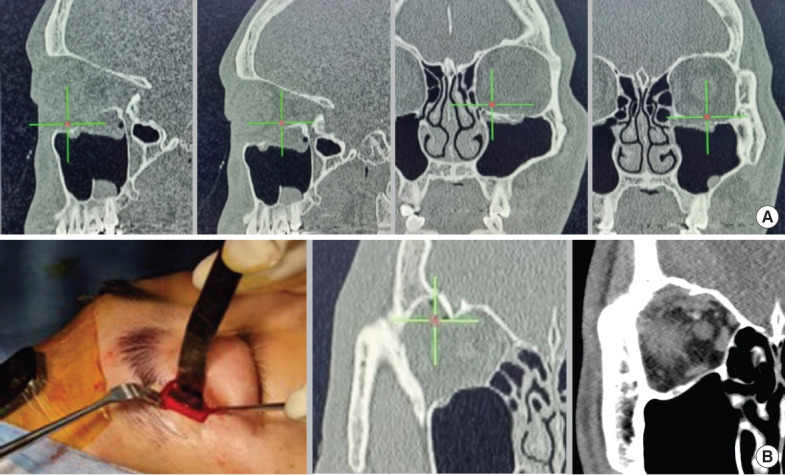

Craniofacial surgery requires comprehensive anatomical knowledge of the head and neck to ensure patient safety and surgical precision. Over recent decades, there have been significant advancements in imaging techniques and the development of real-time surgical navigation systems. Intraoperative navigation technology aligns surgical instruments with imaging-derived information on patient anatomy, enabling surgeons to closely follow preoperative plans. This system functions as a radiologic map, improving the accuracy of instrument placement and minimizing surgical complications. The introduction of first-generation navigation systems in the early 1990s revolutionized surgical procedures by enabling real-time tracking of instruments using preoperative imaging. Initially utilized in neurosurgery, intraoperative navigation has since become standard practice in otolaryngology, cranio-maxillofacial surgery, and orthopedics. Since the 2000s, second-generation navigation systems have been developed to meet the growing demand for precision across various surgical specialties. The adoption of these systems in craniofacial surgery has been slower, but their use is increasing, particularly in procedures such as foreign body removal, facial bone fracture reconstruction, tumor resection, and craniofacial reconstruction and implantation. In Korea, insurance coverage for navigation in craniofacial surgery began in 2021, and new medical technologies for orbital wall fracture treatment were approved in August 2022. These technologies have only recently become clinically available, but are expected to play an increasingly important role in craniofacial surgery. Intraoperative navigation enhances operative insight, improves target localization, and increases surgical safety. Although these systems have a steep learning curve and initially prolong surgery, efficiency improves with experience. Calibration issues, registration errors, and soft tissue deformation can introduce inaccuracies. Nonetheless, navigation technology is evolving, and the integration of intraoperative computed tomography data holds promise for further enhancements of surgical accuracy. This paper discusses the various types and applications of navigation employed in craniofacial surgery, highlighting their benefits and limitations.